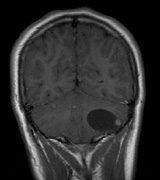

Optic nerve gliomas may involve the optic chiasm and be associated with endocrine disorders or nystagmus.68–70 Surgical excision of chiasmal gliomas (Fig. 6) carries a high risk of visual loss. Invasion of the hypothalamus or the third ventricle carries a poor prognosis, with greater than 50% 15-year mortality rate.71 One review of radiation treatment for chiasmal gliomas collated data from small case series and found no significant long-term improvement in visual function, progression, or mortality with radiation treatment.71 Other reports suggest that radiation doses over 4500cGy improve symptoms and slow progression of chiasmal gliomas over several years.72 Adequate tumor coverage by radiotherapy results in irradiation of normal brain and nearly all children need hormone replacement.73 Chemotherapy is an alternative.74,75

|

- Schwannomas most commonly affect the fifth cranial nerve (CN), but

any cranial nerve may be affected. In contrast to vestibular

schwannomas (CN VIII), these typically do not grow large.84,90 Vestibular schwannomas (acoustic neuromas) are the classic finding

in NF2 (Fig. 7). The risk for malignant transformation is low, but may be higher

with radiation exposure.84,94

- Meningiomas are most likely to affect the spinal cord and supratentorial

part of the cranium.84

- Other tumors: low-grade ependymomas and gliomas may affect the cervical

spine and Brainstem (Fig. 7).84